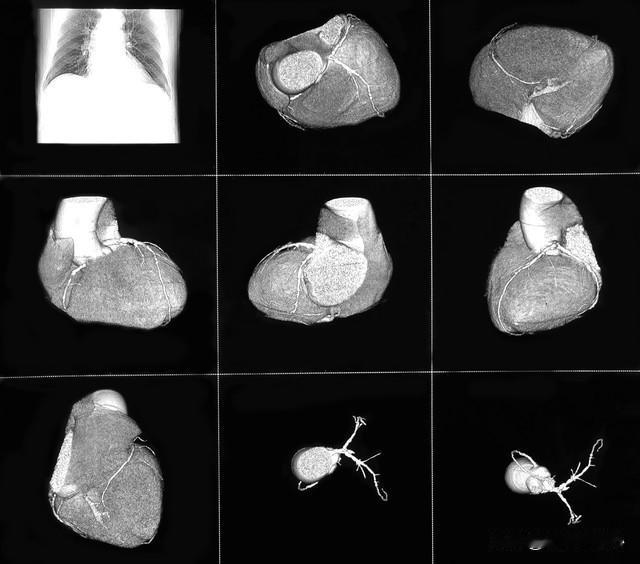

心衰患者的心房可以大到什么程度?

61 岁女性患者,因心衰持续性快速性房颤,到急